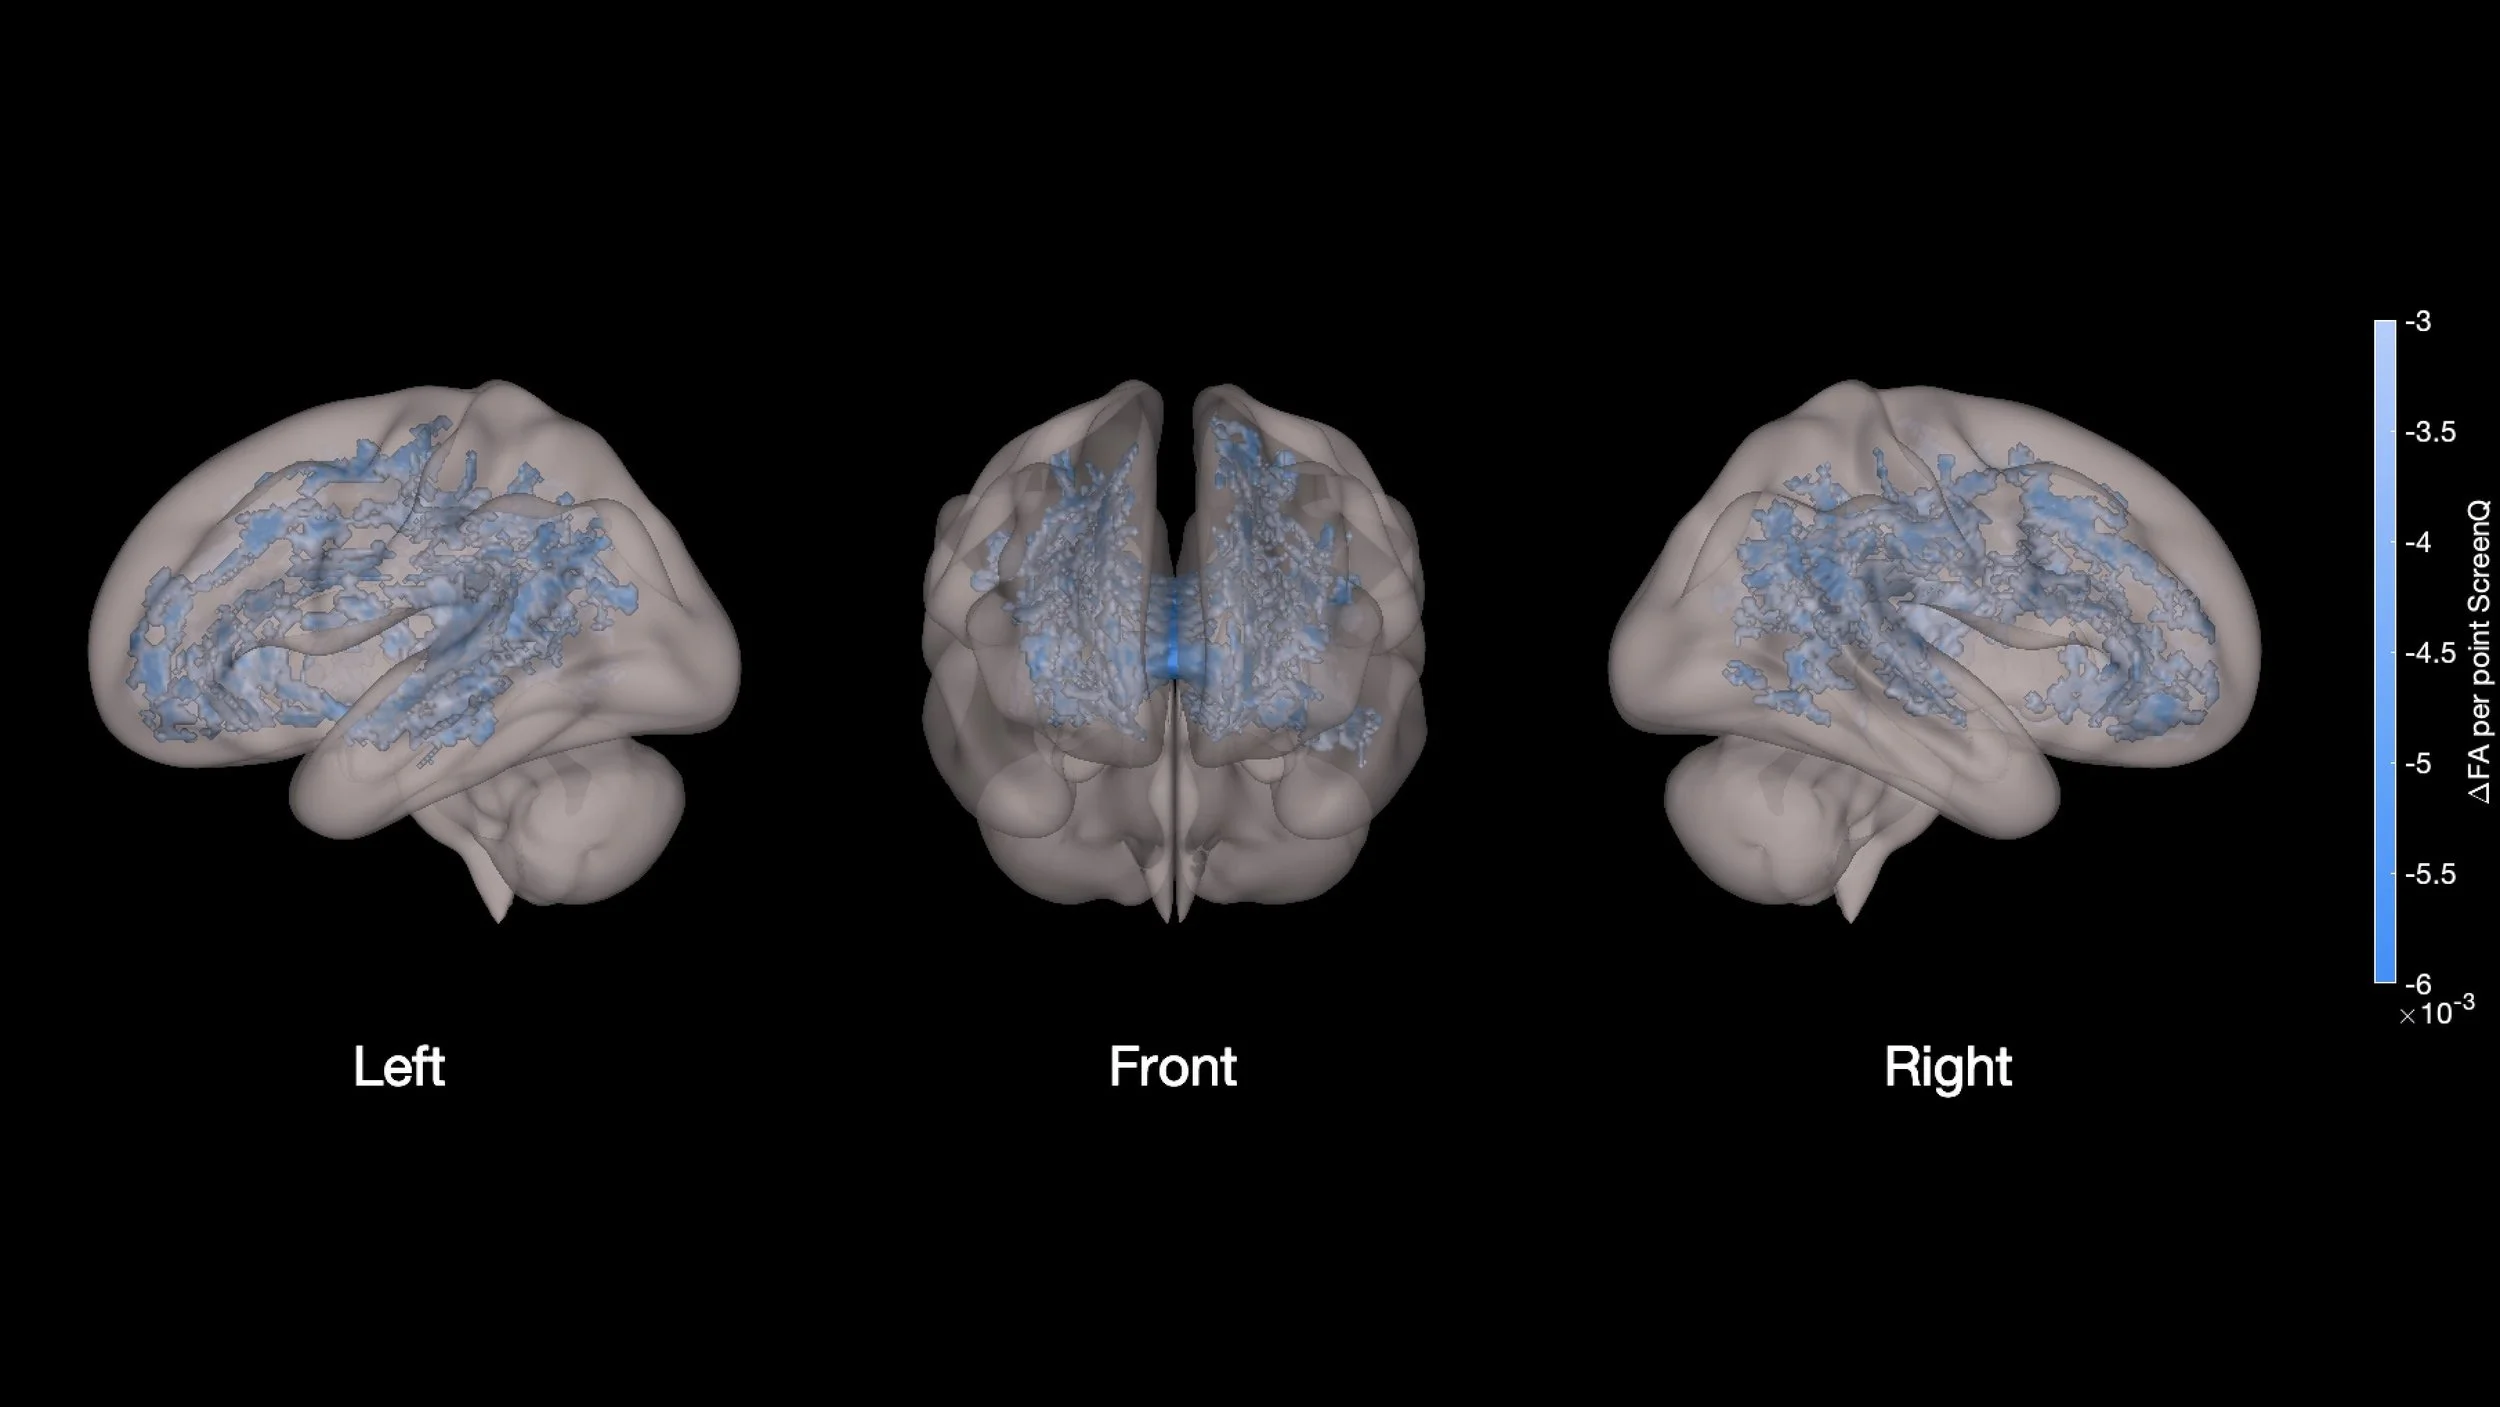

Now, regarding the second set of images, they depict results obtained using a different technique called Tract-Based Spatial Statistics (TBSS) (Hutton et al., 2020). TBSS is still based on DTI data but utilizes a different analytical approach. Instead of directly analyzing FA and RD values across the brain like in the first set of images, Tract-Based Spatial Statistics (TBSS) typically involves aligning the DTI data from multiple individuals onto a common template or skeleton. This process allows researchers to compare and analyze white matter integrity across all subjects in a standardized way. So, while both sets of images involve DTI and analyze FA and RD, they utilize different analytical methods (standard analysis vs. TBSS) to examine how screen media use influences white matter integrity in preschool-aged children.

The lateral and medial views allow researchers to observe which tracts are particularly affected by screen media use and how these alterations are distributed throughout the brain (Hutton et al., 2020). The data from all 47 preschool-aged children are combined and analyzed together. The color-coded areas on the brain represent regions where differences in Fractional Anisotropy (FA) or Radial Diffusivity (RD) values are observed across the entire group in relation to their screen media use.

TBSS and DTI both provided complementary information about the association between screen media use and alterations in white matter integrity. Both techniques revealed that higher ScreenQ scores, indicating increased screen media exposure, were correlated with changes in Fractional Anisotropy (FA) and Radial Diffusivity (RD) values in specific brain regions.

While DTI focused on analyzing the overall white matter integrity across the brain, TBSS specifically identified regions where these alterations were most pronounced. So, in a sense, TBSS reaffirmed the findings observed through DTI by pinpointing specific areas of the brain where the effects of screen media exposure were most notable.

This data collected from the study makes this image a gold mine (Hutton et al., 2020). We're able to observe the distinct effects on Fractional Anisotropy (FA) and Radial Diffusivity (RD) whilst also knowing the major functions that these different tracts serve. Given our knowledge of these major functions from previous brain studies, the observed increases and decreases in FA and RD become meaningful in terms of the specific functions being affected. The ability to interpret these increases and decreases in FA and RD—and to correlate them with the rise in screen time observed in our sample of 47 children—makes this image incredibly valuable.

The impact of books on a child’s brain. Look at all that red - an increase in organized white matter (we know what that means now!)

Now that we’ve become experts on interpreting MRIs and their different types, you might think understanding these images should be easy! Just kidding—it likely takes professionals a lot of practice to interpret them correctly. However, the images we have come from researchers skilled in this area, drawn from three studies. Two of these studies link a child’s brain development to technology use (images 1 and 3), and another study connects a child’s brain activity to reading books. Delving deeper into this specific book research article would be fascinating. Interestingly, the middle image shows an increase in organized white matter in areas marked by red spots. This is very promising for young children and almost the opposite of what we've discussed regarding screen time — the articles are linked to the images if you’d like to read!